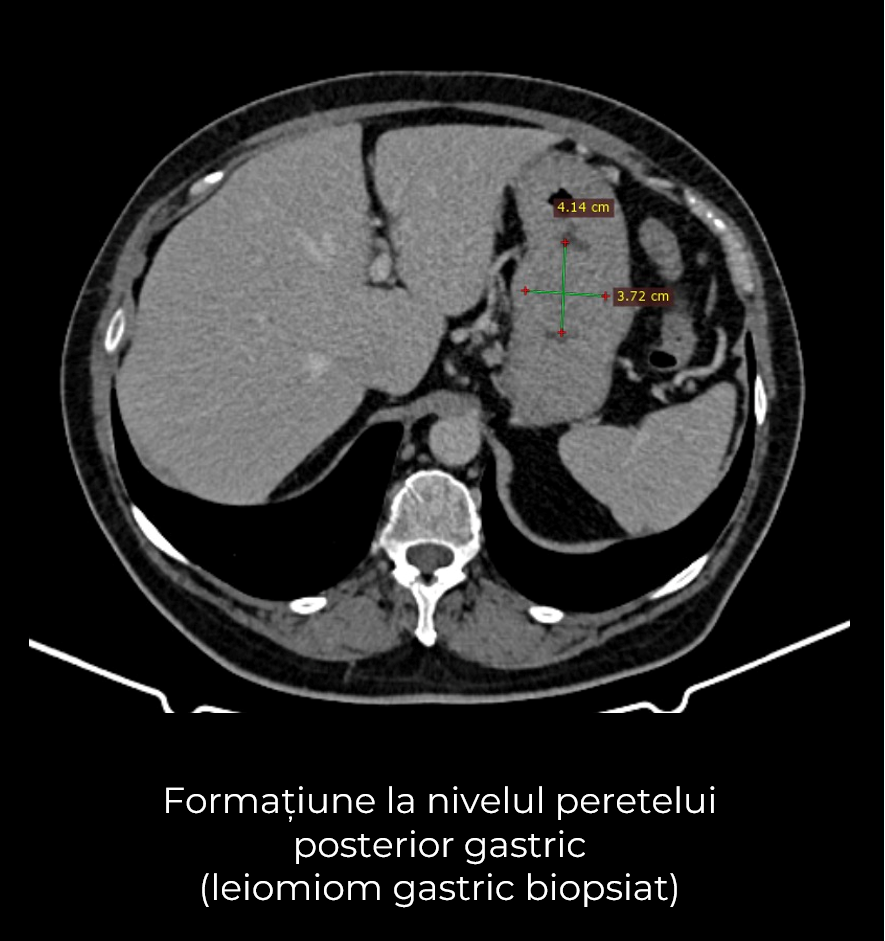

Uneori, o durere aparent banală ascunde în spate o realitate medicală mult mai serioasă. Așa s-a întâmplat și în cazul unei paciente de 63 de ani, care a ajuns la spital pentru dureri pelvine persistente. Investigația CT a schimbat însă complet perspectiva: au fost descoperite trei formațiuni tumorale în zone diferite ale corpului – o tumoră mamară stângă (carcinom mamar invaziv biopsiat), o tumoră pelvi-abdominală voluminoasă (tumoră ovariană) și o formațiune la nivelul peretelui posterior gastric (leiomiom gastric biopsiat).

- Gastrectomie segmentară – excizia porțiunii afectate din stomac